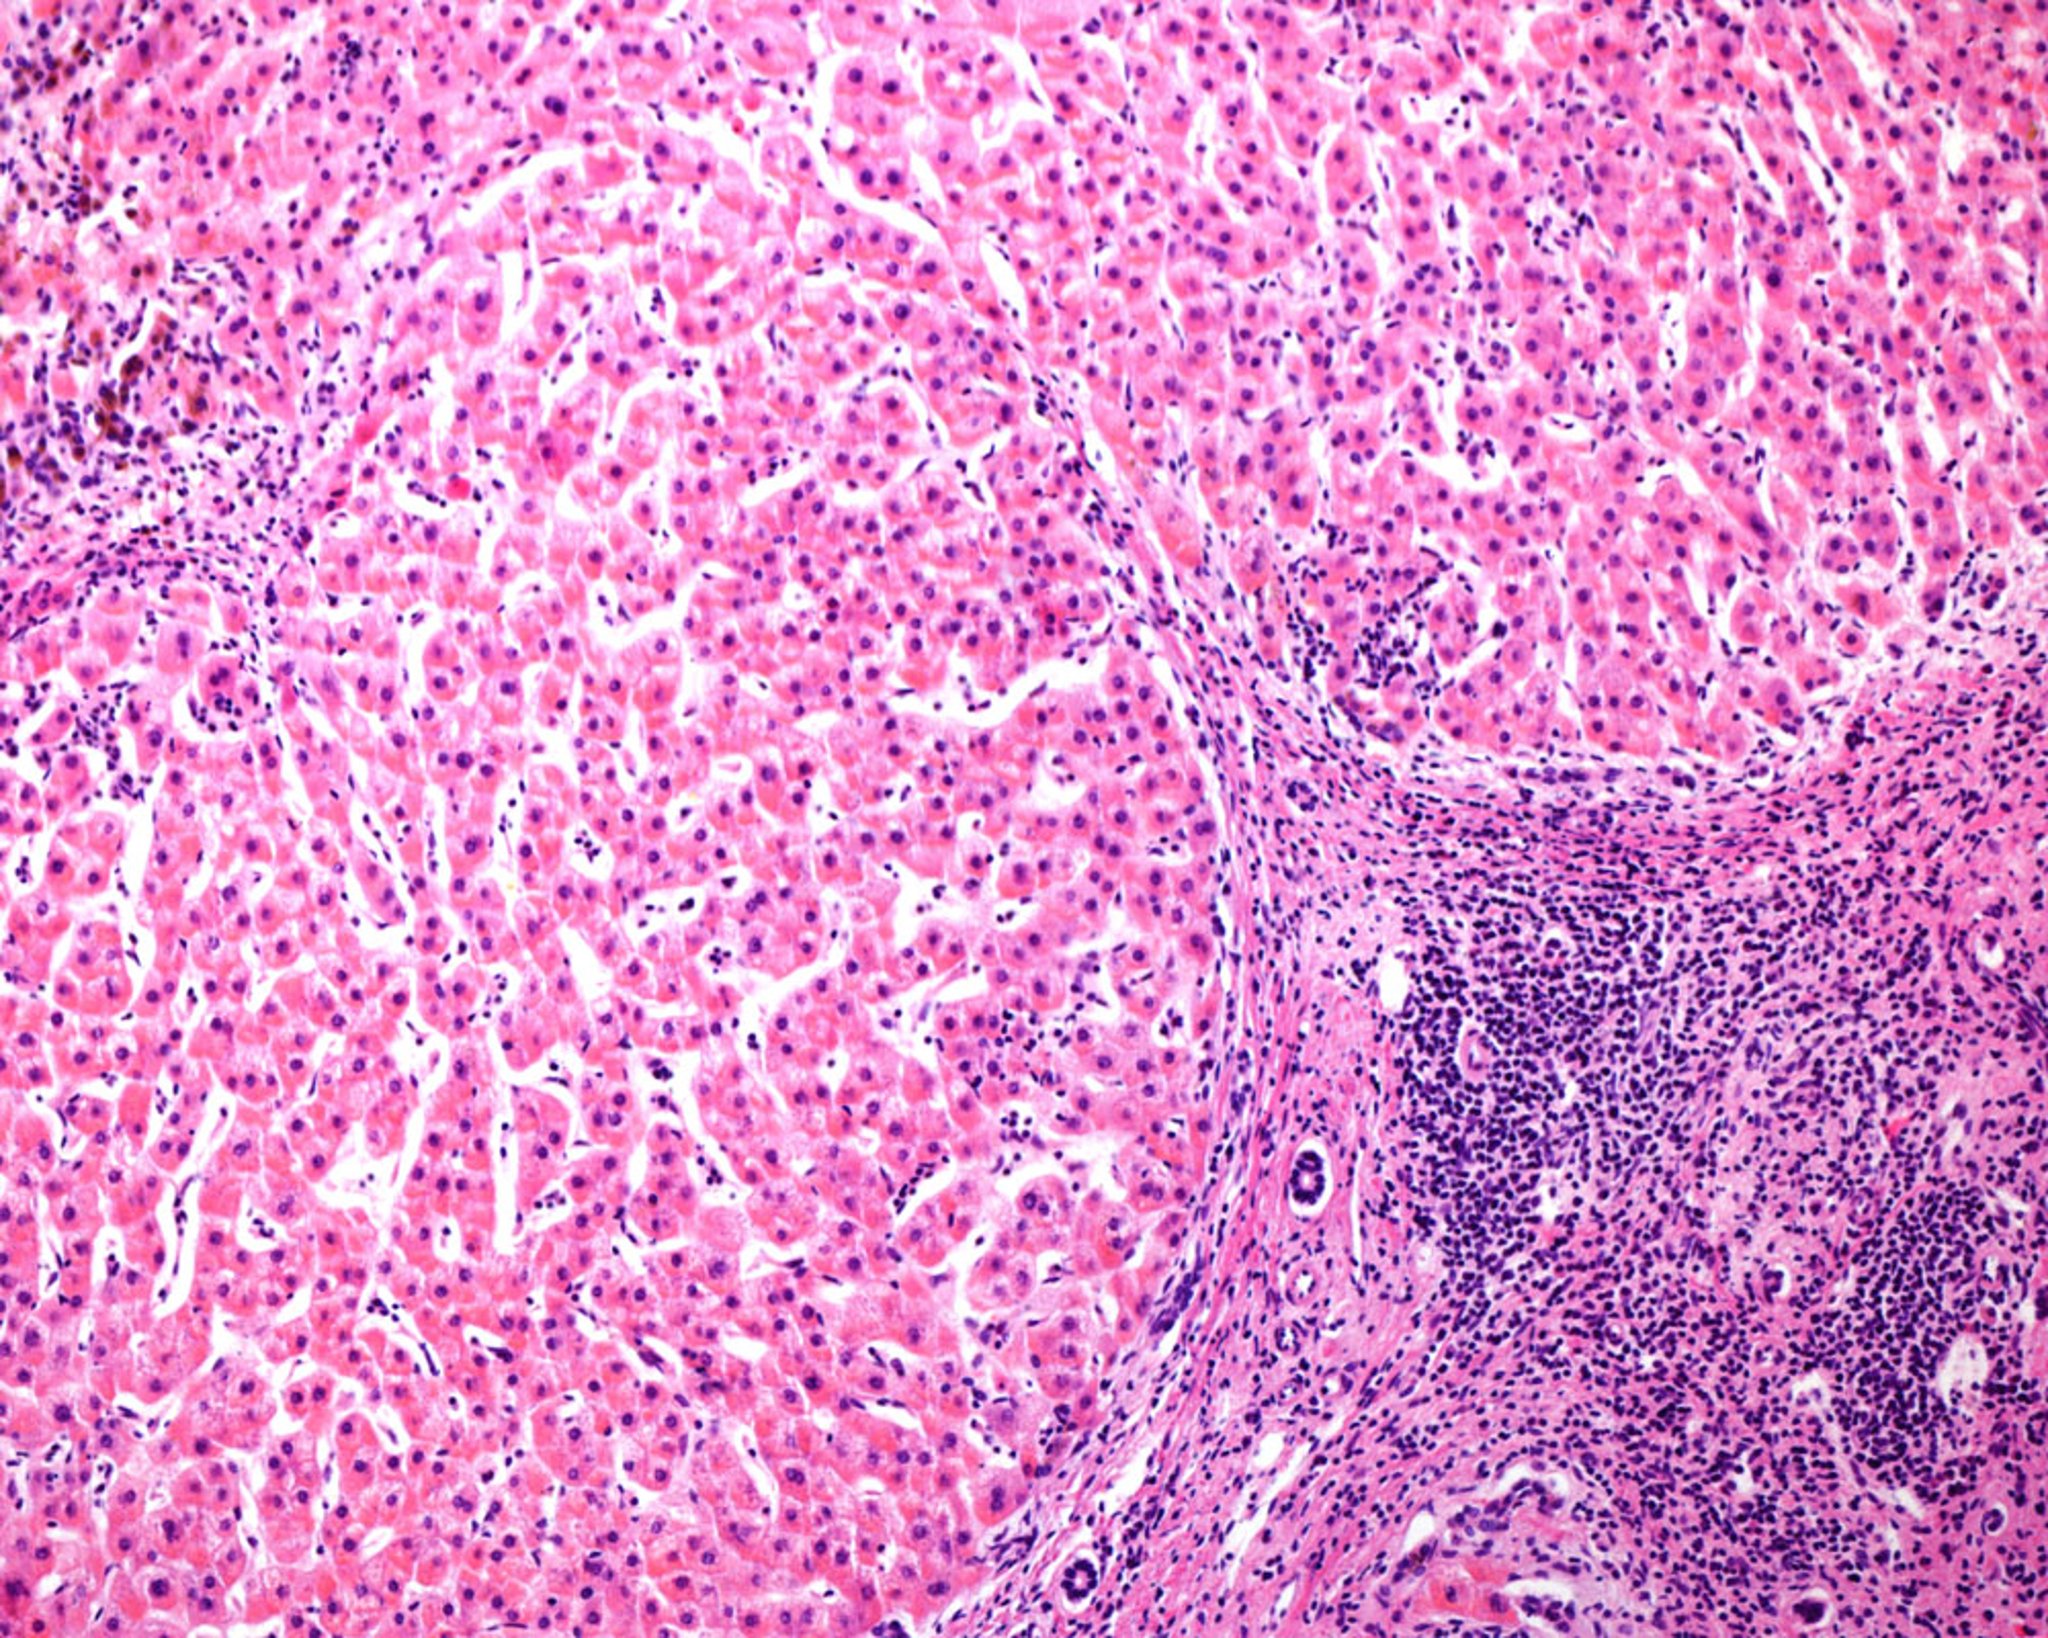

Micronodular Cirrhosis in Human Liver (Light Micrograph)

Light micrograph of a human liver with micronodular cirrhosis, a frequent consequence of alcoholic hepatitis. The regenerating nodules are separated by connective tissue septa showing chronic inflammatory infiltrates. Note the absence of a central vein in the nodules and of portal triads in the connective tissue septa.